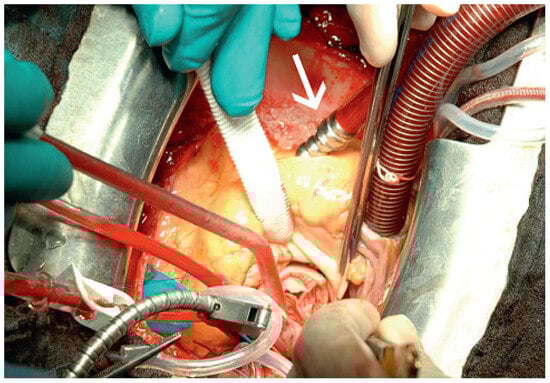

Muscular Ventricular Septal Defect After Mitral and Aortic Valve Replacement